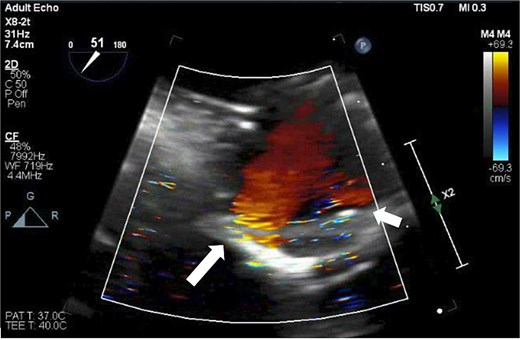

After the aortic cross-clamp was removed, transesophageal echocardiogram (TEE) demonstrated what was suspected to be a mild-to-moderate paravalvular leak along the non/right coronary cusp commissure. The jet appeared highly eccentric and perpendicular to the flow of the left ventricular outflow tract (Fig. 1). Given the size of the leak, it was decided to rearrest the heart. After reopening the aortotomy and assessing the bioprosthesis, no valve defects were seen. But given the suspected friable and thin annular tissue, the base of the aorta was further reapproximated and reinforced to the external sewing ring at the right/noncoronary commissure with multiple prolene, pledgeted sutures. After the second cross-clamp was removed, TEE demonstrated a larger, now broad-based, moderate or greater regurgitant leak at the non/right commissure, and, in addition, the presence of a new mild leak along the left/right commissure (Fig. 2). At this point, a transprosthetic leak was suspected with potential malfunction of the valve. The heart was rearrested for a third time, and the bioprosthetic valve was reexamined and annulus probed. The valve was explanted without any annular pathology being evident, and examination of the valve on the back table demonstrated a torn area of cloth along the right/non and left/right commissures of the cuff at the level of the stent posts, suspected to be the site of the leaks (Fig. 3). A new same-sized 27 mm Inspiris Resilia valve was chosen, and the valve was placed on to the annulus in a supra-annular fashion with multiple ventricularly based 2-0 Ethibond EXCEL pledgeted mattress sutures, and secured with the COR-KNOT device.

TEE demonstrating two leaks from the Inspiris Resilia valve after the second aortic cross-clamp was removed. A larger now broad-based, moderate or greater regurgitant leak at the non/right commissure (long arrow), and a new mild leak along the left/right commissure (short arrow).